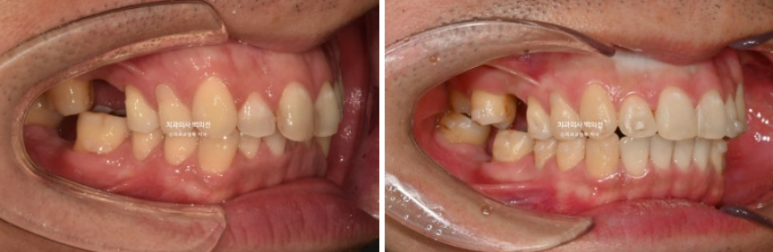

사진에 듬성듬성 보이는 총 3군데의 빈공간은 어금니가 없는 상태입니다.

언젠가는 임플란트를 해야지 하고 없는 채로 시간이 흘러 주변 어금니들이 빈공간으로 쓰러진 상태입니다.

24.05~24.11

교합은 좋습니다.

24.05~25.03